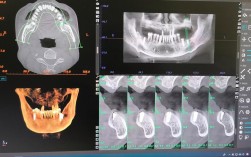

种植牙和CT(特别是锥形束CT,CBCT)之间有着极其密切且至关重要的关系,可以说,CBCT是现代种植牙成功实施和保障安全的基石之一。

种植牙是一项精密的手术,需要详细的三维影像信息来指导,而CBCT正是提供这种信息的关键工具。

- 三维 vs 二维: 普通X光片是二维重叠影像,容易产生结构重叠,难以准确判断骨量、重要结构的精确位置和深度,CBCT提供的是高分辨率的三维立体图像,没有结构重叠,空间定位极其精确。

- 信息量: CBCT提供的信息远比二维片丰富和准确,是制定复杂种植方案不可或缺的工具。

- 精准测量: CBCT软件可以进行精确的线性、角度、体积测量。